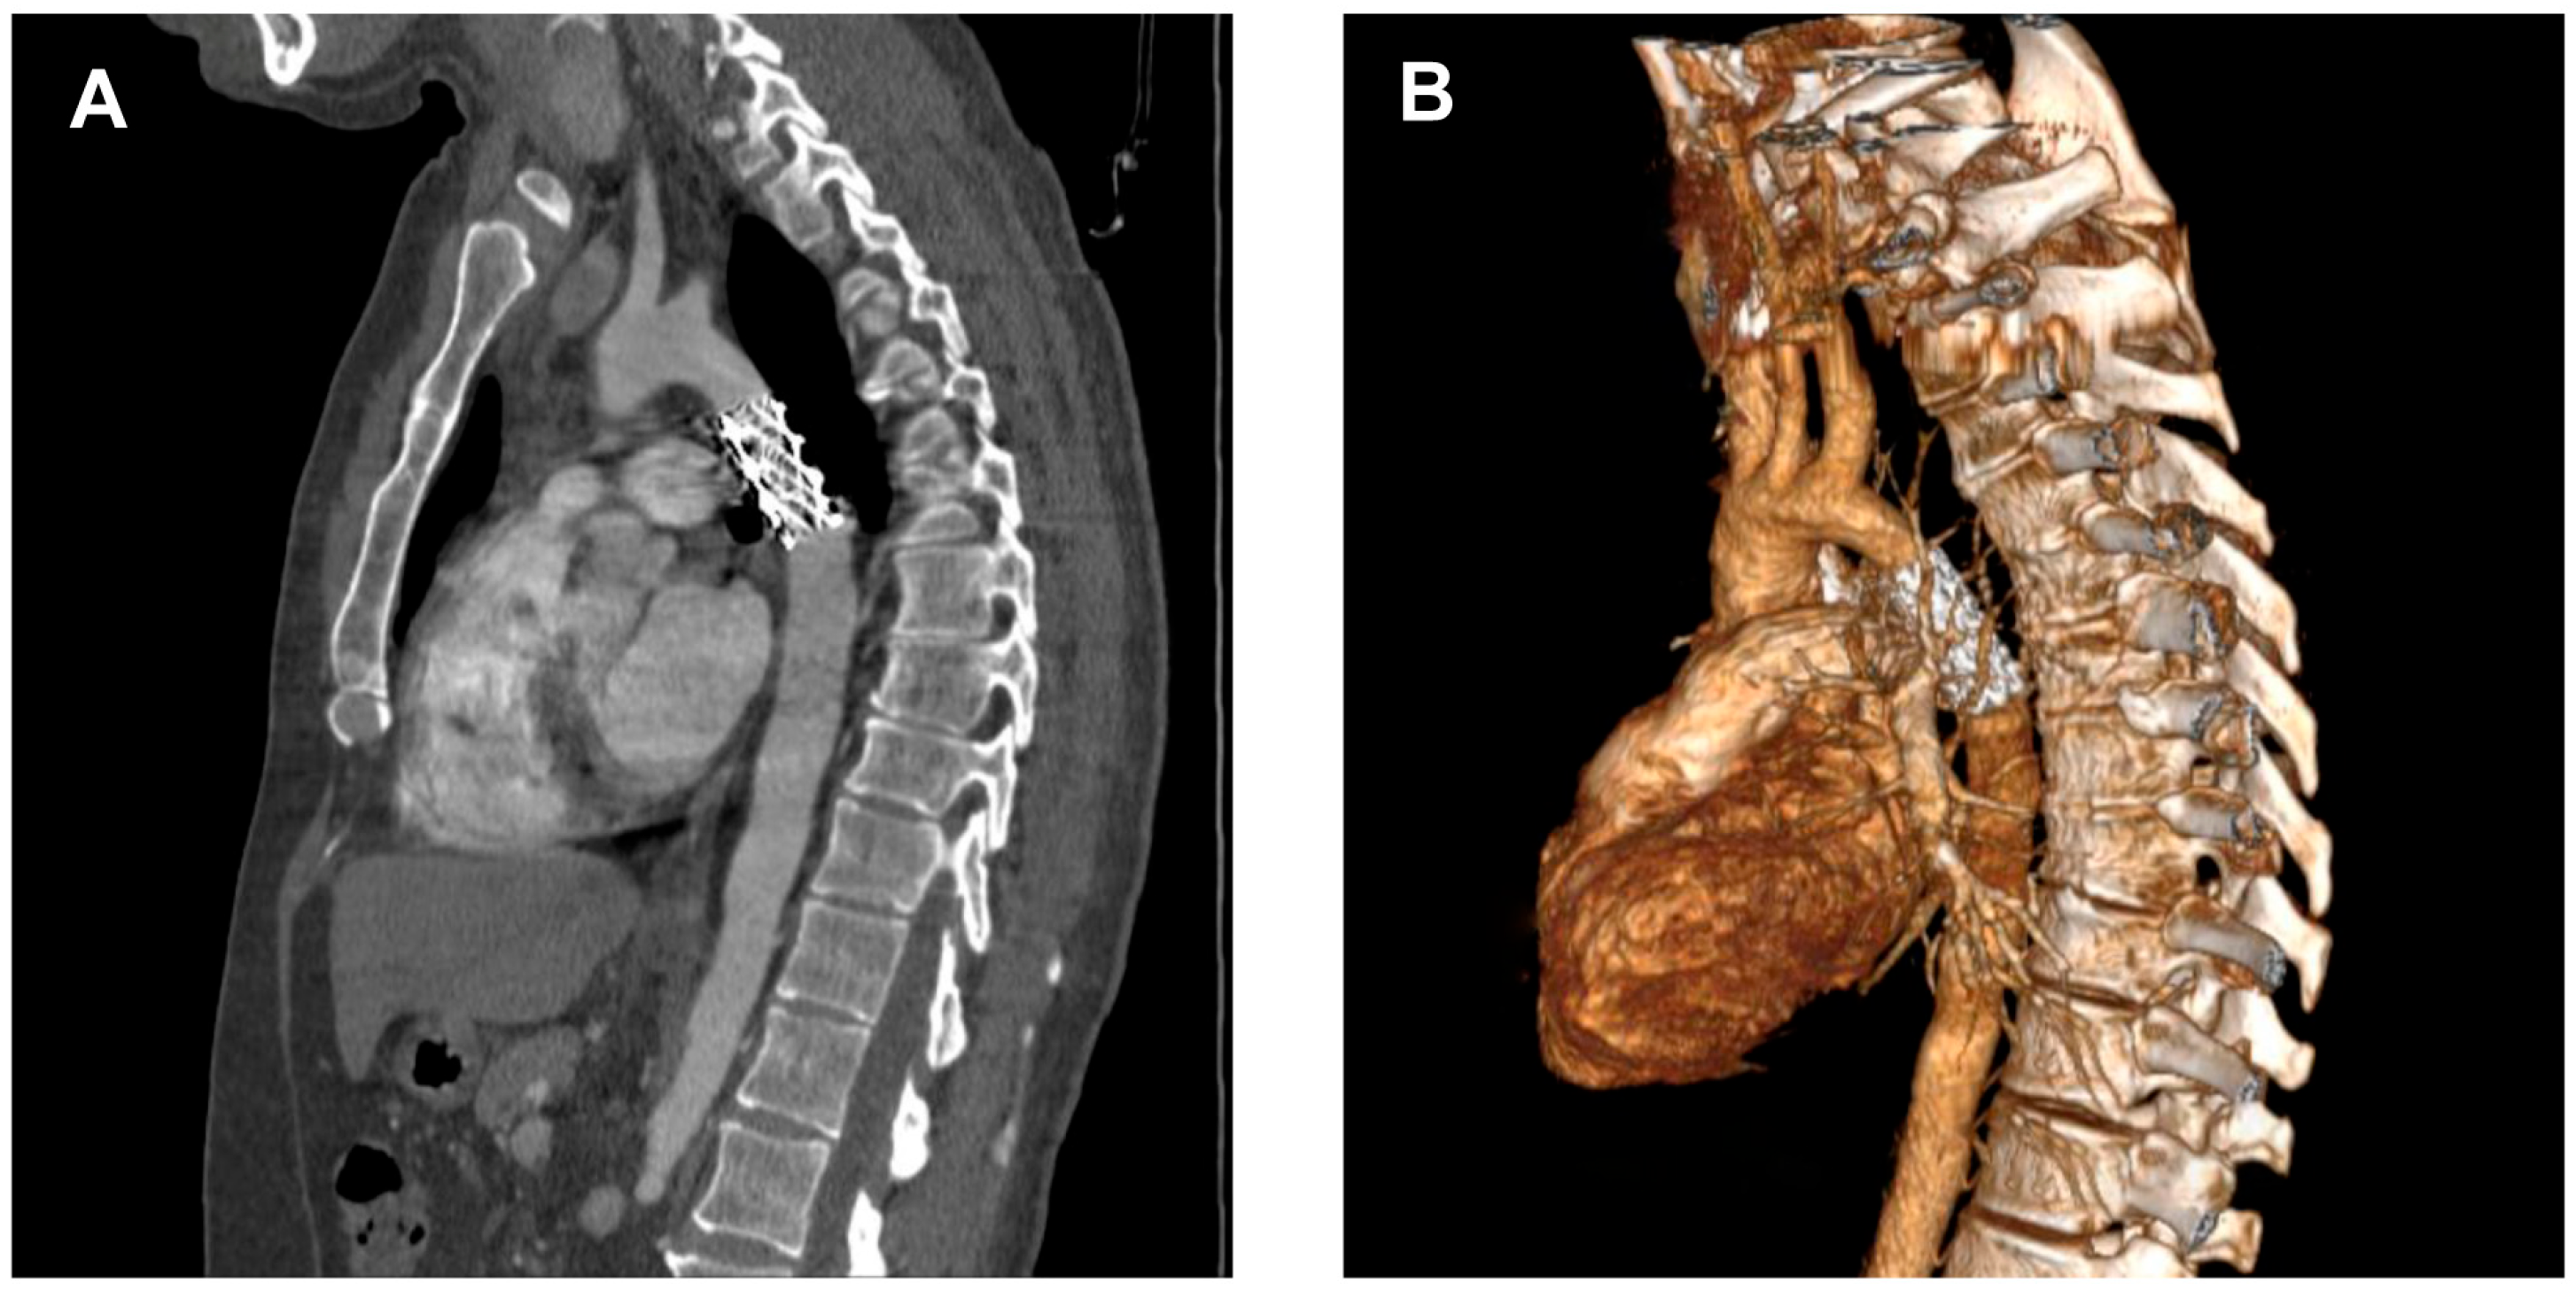

Transthoracic echocardiography (Figure 2) may reveal signs of left ventricular hypertrophy and diastolic dysfunction from the apical and parasternal views, while the suprasternal view may identify the aortic atretic segment. However, the presence of collateral circulation is difficult to identify using this technique [21].

Diagnosis is often incidental, made during workup for hypertension or vascular complaints, and confirmed by imaging (CT—Figure 3, MRI, echocardiography) showing the atretic aortic segment and collateral vessels.